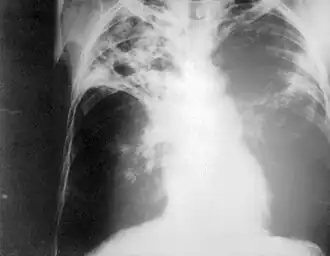

Chest radiography showing advanced bilateral pulmonary tuberculosis. Source: CDC

Purposemass screening for tuberculosis

Chest photofluorography, or abreugraphy (better known as mass miniature radiography in the UK and miniature chest radiograph in the US), is a photofluorography technique for mass screening for tuberculosis using a miniature (50 to 100 mm) photograph of the screen of an X-ray fluoroscopy of the thorax, first developed in 1936.